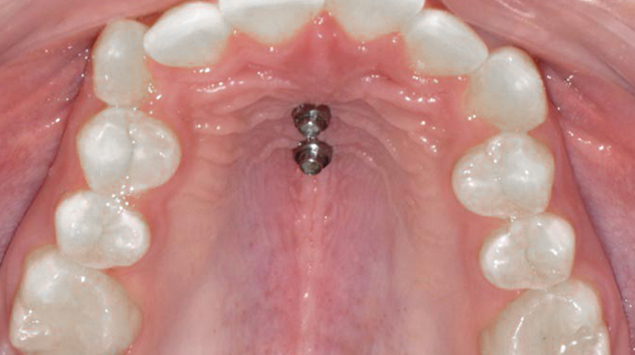

>   Beneslider na podniebieniu.